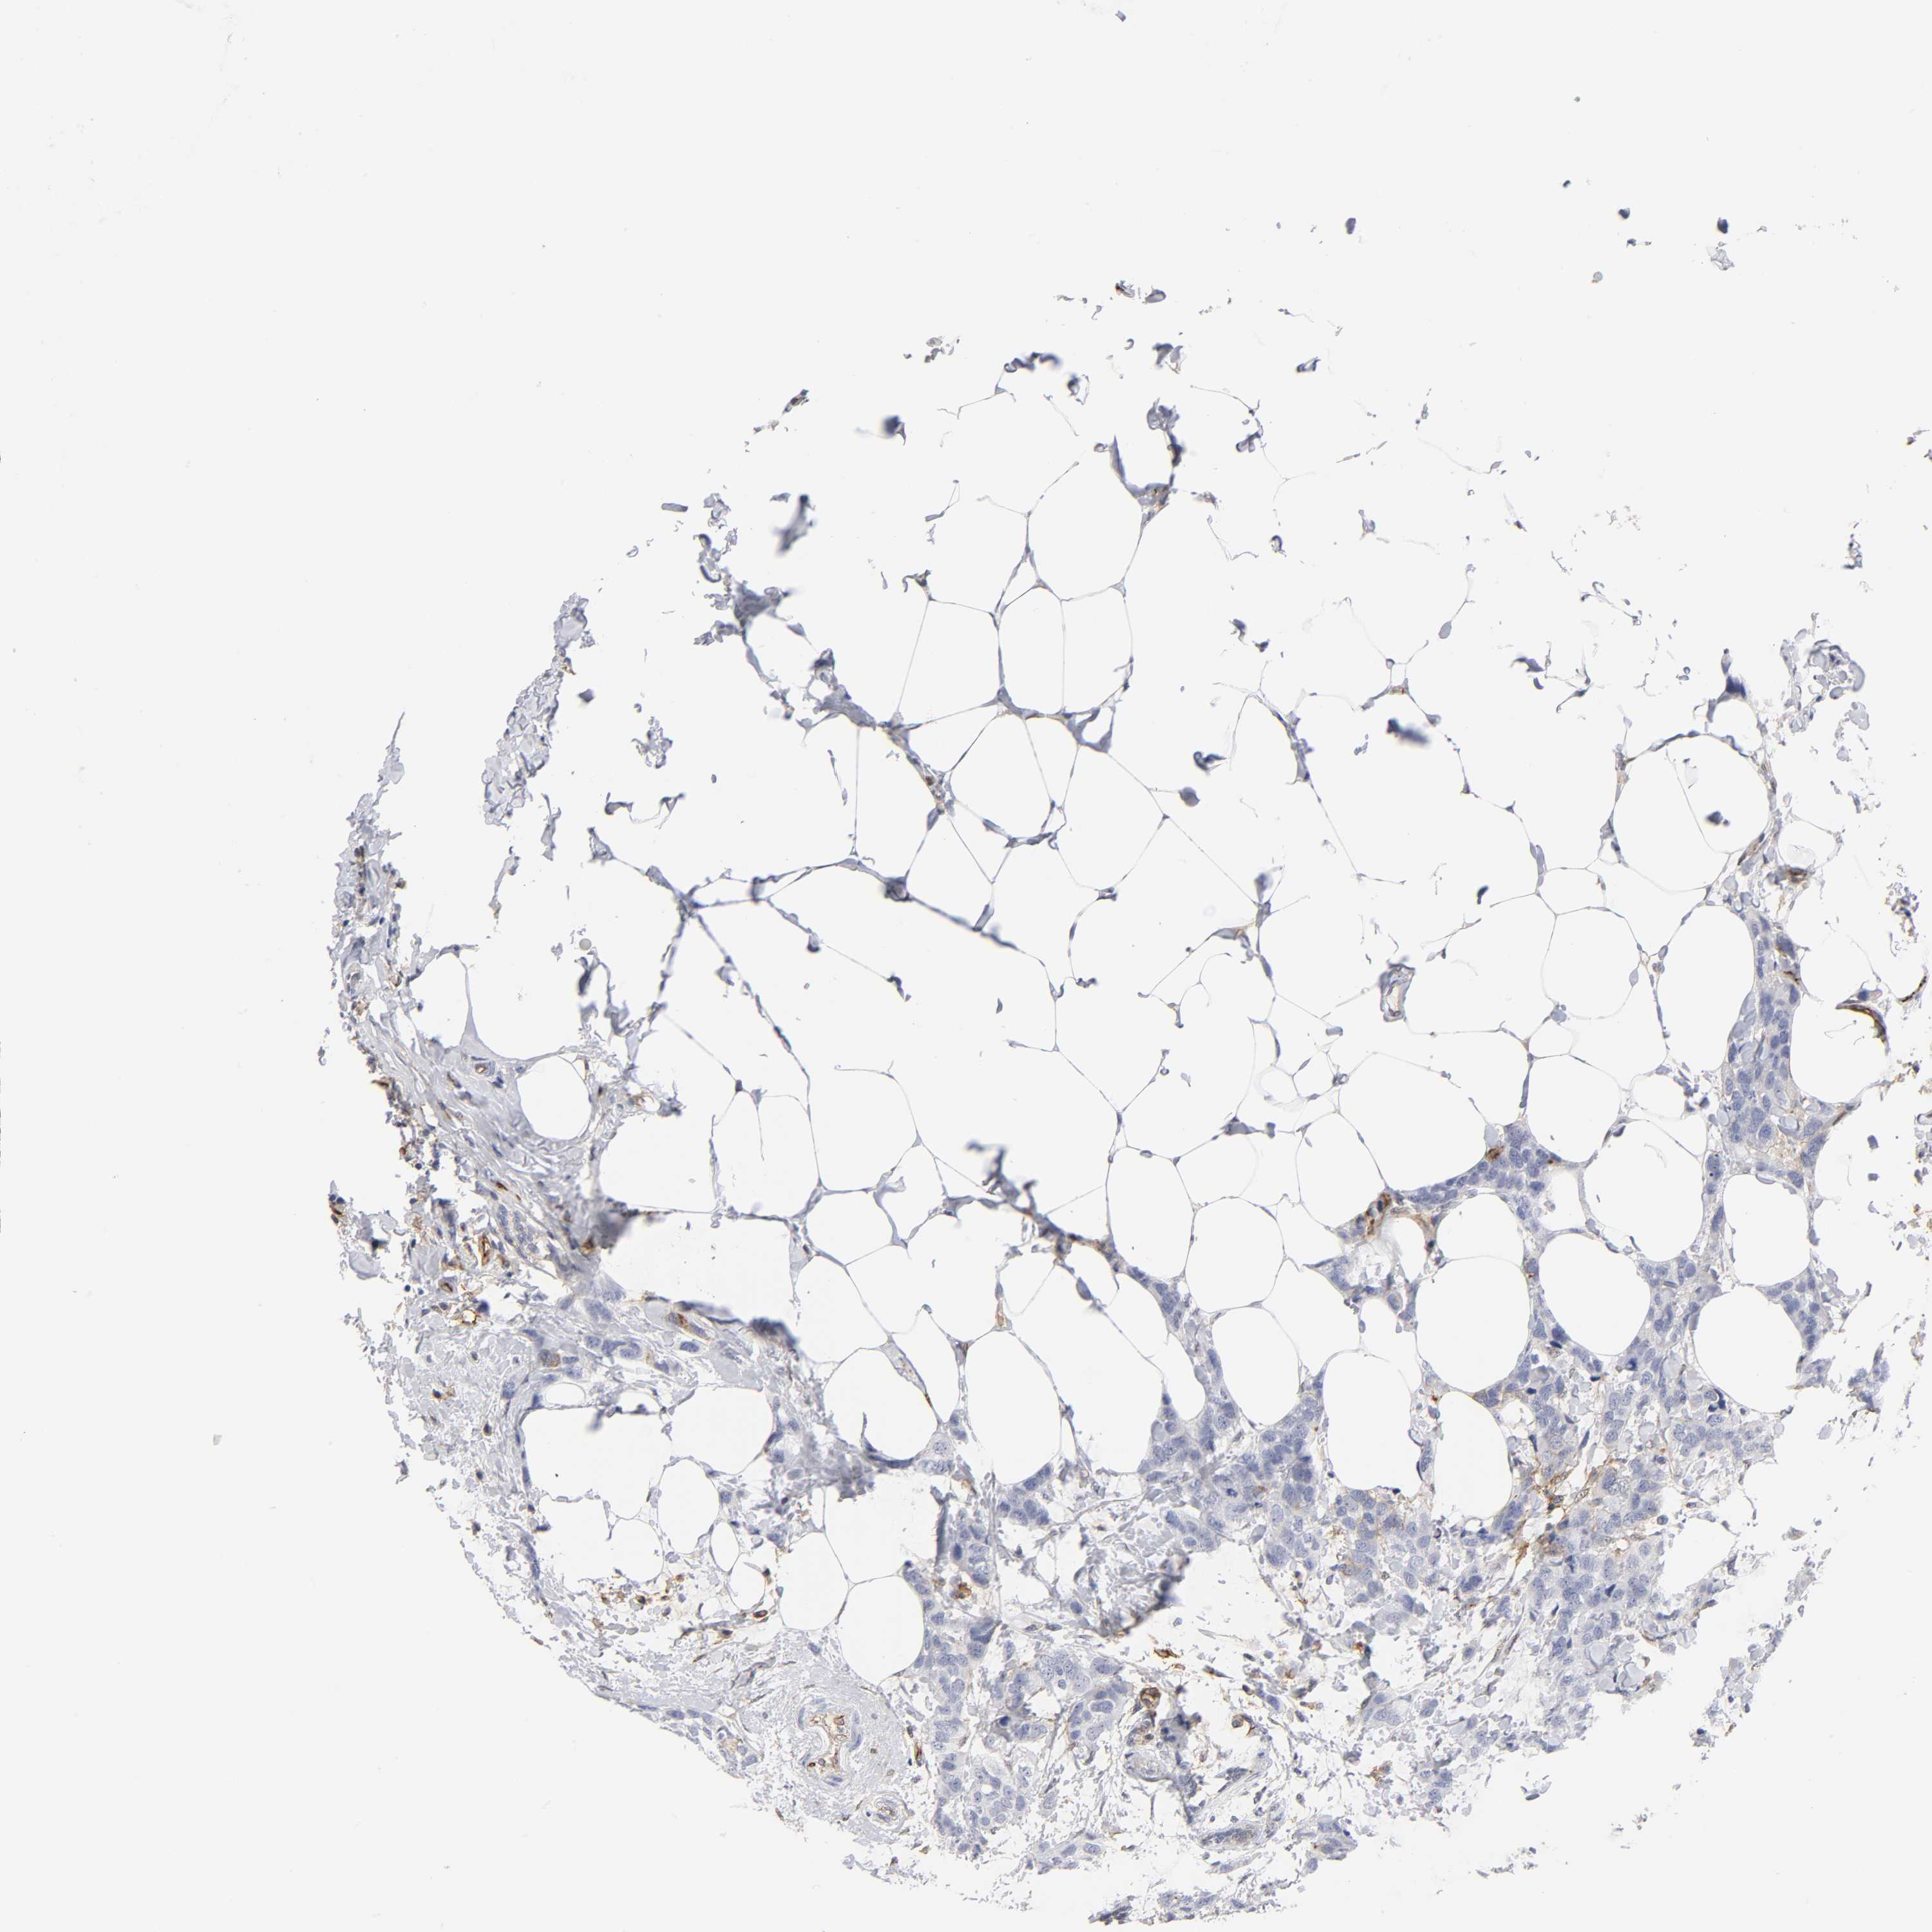

BRCA TCGA BRCA VALIDATION PROTEIN EXPRESSION

ANTIBODIES

AND

VALIDATION